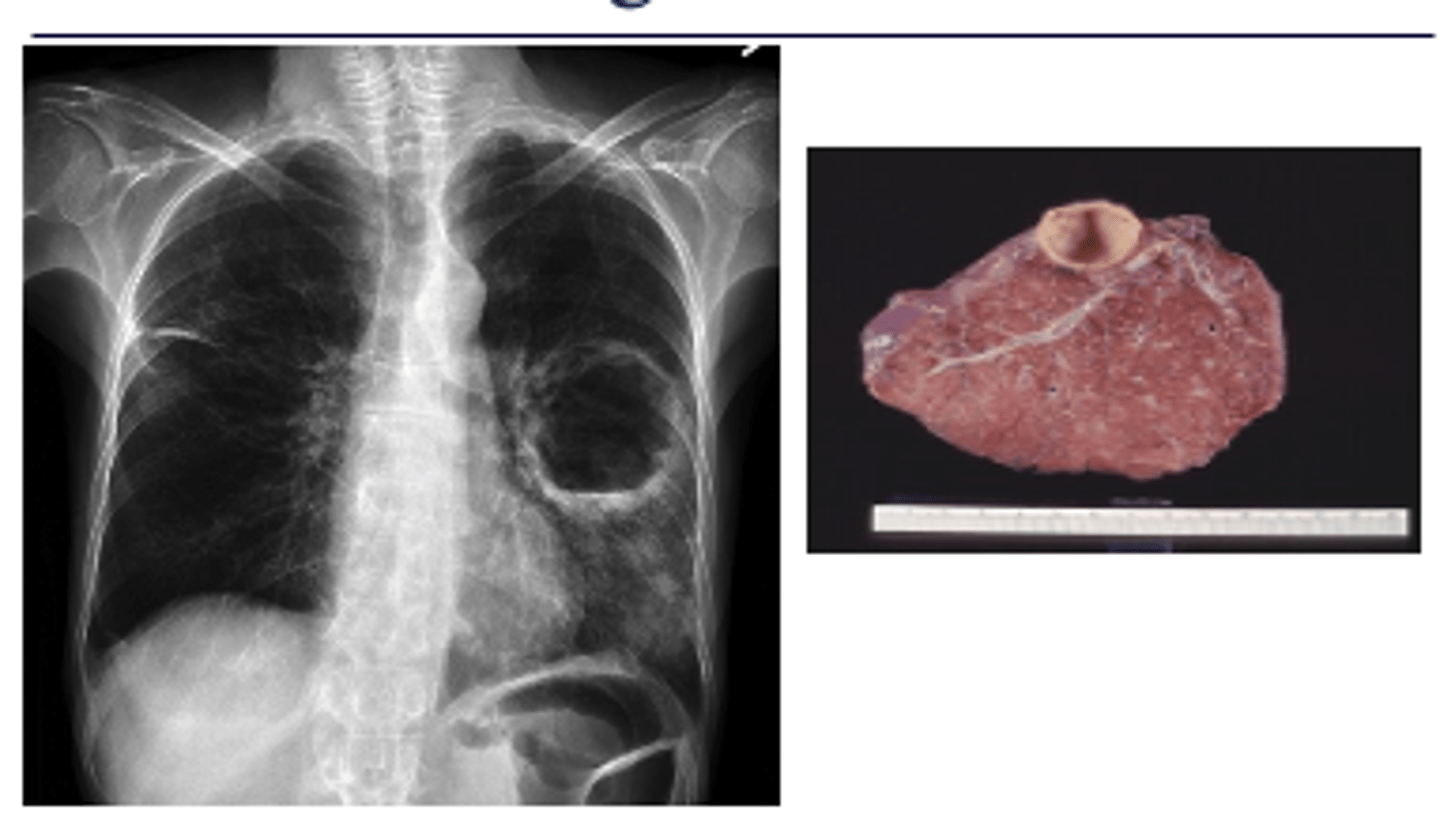

New cards

What is cavitary TB? What will X-ray look like?

oCavitary TB is also a late phase of TB.

oHealing leads to fibrososis and calcifications which may pull the hilum up on the affected side.

X-ray will have dark spots indicating holes/cavities

<p>oCavitary TB is also a late phase of TB.</p><p>oHealing leads to fibrososis and calcifications which may pull the hilum up on the affected side.</p><p>X-ray will have dark spots indicating holes/cavities</p>